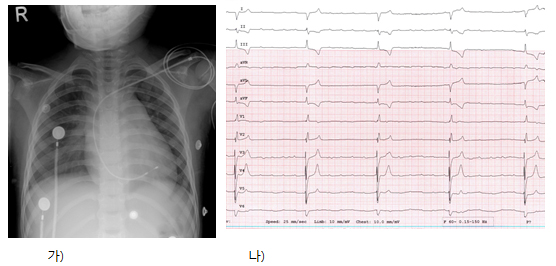

±×¸² 1. (°¡) ÈäºÎ»çÁø. ÁߵÀÇ ½Éºñ´ë ¼Ò°ß°ú Æó¿ïÇ÷ ¼Ò°ßÀÌ °üÂûµÈ´Ù. Àӽà ½ÉÀå ¹Úµ¿±â µµ°üÀÌ »ðÀԵǾîÀÖ´Ù. (³ª) ½ÉÀüµµ»ó ¿ÏÀü ¹æ½Ç Â÷´Ü°ú ½É½Ç ÀÌÅ» ¹Úµ¿ÀÌ °üÂûµÇ¸ç ½ÉÇÑ ¼¸Æ ¼Ò°ßÀÌ °üÂûµÈ´Ù.